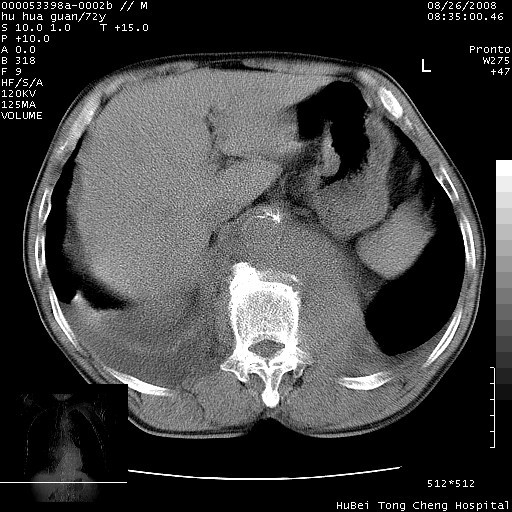

可以明确的说。肯定不是主动脉夹层破裂出血!考虑为淋巴瘤或间叶组织来源的恶性肿瘤可能性大。右肺小结节建议薄层观察,如能发现恶性征象,那椎前改变就考虑为转移所致。至于双侧少量胸水乃静脉血回流受阻所致。

图像及窗宽窗位均不理想。周围性肺癌/胸腔积液/纵隔积液。

1、右肺周围性肺癌、胸腔积液(双)

2、建议食道吞钡和增强检查排除食道和主动脉病变

3、后纵隔淋巴类肿瘤

1、右上肺结节病变,肺泡癌不除外,请随诊;左下肺近后纵隔病变,考虑纵隔型肺癌侵犯大血管可能;

2、右下肺背段少许炎症,双侧胸腔积液,右下肺纤维索条。

降主动脉前移位,后纵隔占位

后纵隔占位,降主动脉前移位;双侧胸腔积液;应排外食管病变侵犯血管可能;